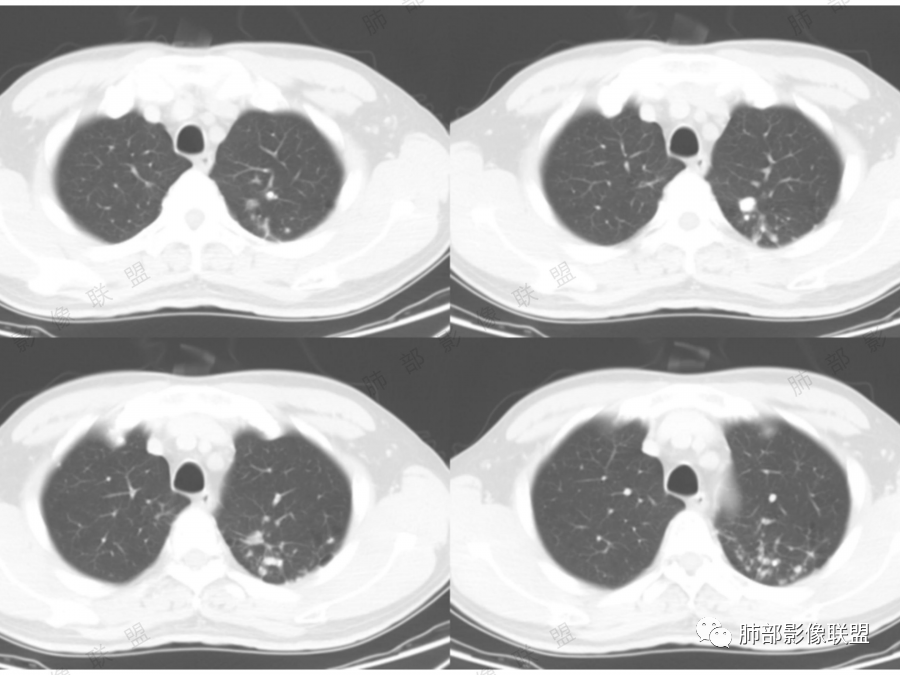

孤立性的多囊型病变伴分隔。ccam,肺隔离征,囊性肺癌,闭锁。。这是大家上面写的。看看怎么排除。血管看到肺动脉进入供血,没有感染液平,肺隔离不符合。没有代偿肺气肿,支气管没有闭锁,闭锁不考虑。那锁定ccam和肺癌。我们临床也常见是支气管畸形所致的囊。

我们看哪些内容,第1.周围有没有毛玻璃2.分隔有无粗细不均或结节,壁有无厚薄不均有无壁结节3.支气管,4.随访。

图一看到支气管堵塞,不知道是不假象

图二图三似见毛玻璃

另外分隔比较光滑似无壁结节。

目前可疑恶性,但是证据不足,毛玻璃不够,壁结节及分隔增厚结节不明显。怎么处理,要么随访,如果觉得忍不了也可以切。不会太耽误

@傅昌瑜—贺州市人民医院—呼内 里面的血管进一步支持恶性。但不鉴别腺癌和鳞癌,主要鉴别的,还是多囊,张力较高,囊壁较薄(实变区除外),加GGO。